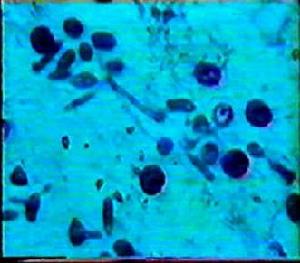

寄生蟲感染寄生蟲的生活史比較複雜,有不同的發育階段。其中能使人體感染的階段稱感染階段或感染期(infectivestage)。寄生蟲侵入人體並能生活或長或短一段時間,這種現象稱寄生蟲感染(parasiticinfection)。寄生蟲感染的結果可因蟲種、宿主的遺傳素質、營養和免疫功能等因素而異。

有的寄生蟲,既可引起皮膚幼蟲移行症又可引起內臟幼蟲移行症,對人體危害較大,應引起足夠的重視。無論是皮膚或內臟幼蟲移行症,在臨床上均可出現明顯的症狀和體徵,且常伴有嗜酸性粒細胞增多、高丙球蛋白血症以及IgE水平升高。有些寄生蟲在常見的寄生部位以外的組織或器官內寄生,這種寄生現象稱異位寄生(ectopicparasitism),由異位寄生引起的損害稱異位損害。了解寄生蟲幼蟲移行症和異位寄生現象,對於疾病的診斷和鑑別診斷至關重要。